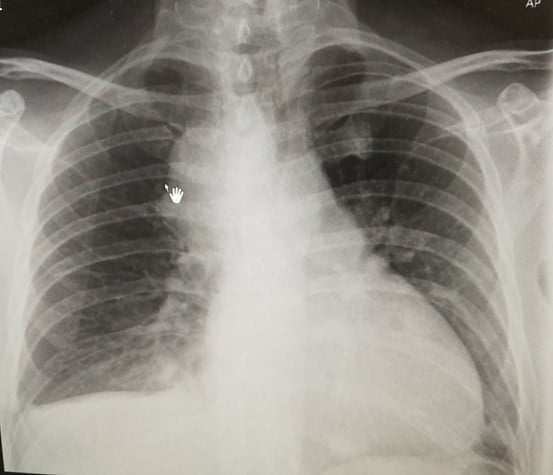

Chest X-Ray Clue

Although the CXR was AP view, cardiomegaly was evident.

This raised concern — and led to a closer look at the ECG.